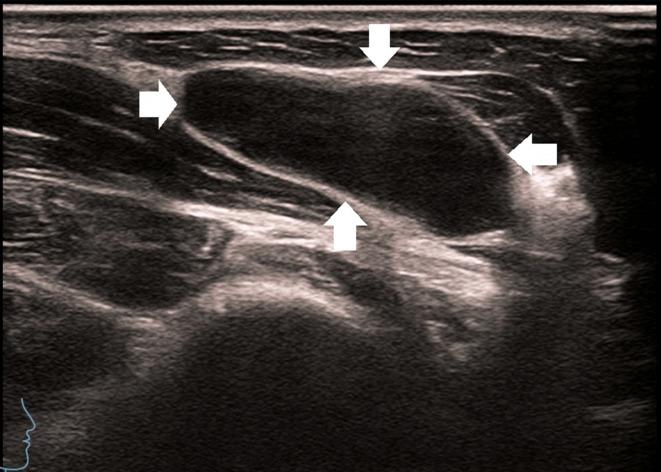

To investigate the value of contrast-enhanced ultrasound (CEUS) assisted core needle biopsy (CNB) in the diagnosis of cervical lymph node tuberculosis (LN TB) and improve the positive rate of cervical LN TB.

We retrospectively analyzed 730 samples obtained from July 2010 to January 2025 from patients treated with effective antituberculosis therapy and with microbiologically confirmed and surgical pathologically proven cervical lymph node enlargement who had undergone CEUS- CNB at our hospital. All patients were divided into two groups according to the historical control method. The CEUS group (2017-2025) underwent CEUS- CNB (485 cases), whereas the US group (2010-2018) underwent US-guided CNB (245 cases). The positive rates of pathological diagnosis and Xpert Mycobacterium tuberculosis complex (MTBC) and resistance to rifampin (RIF) (MTB/RIF) assay diagnoses were compared between the groups.

The specimens' integrity was significantly higher after CNB in the CEUS group than in the US group (CEUS group: 72.30%; US group: 45.49%), and visual satisfaction of sampling in the CEUS group was higher (χ2: 47.651, P < 0.001). Histopathological examination sensitivity, specificity, positive predictive value, and negative predictive value were higher in the CEUS group than in the US group. The sensitivity of the Xpert MTB/RIF assay was significantly higher in the CEUS group than in the US group.

The study results support the clinical use of CEUS for improving the diagnostic performance and positive rate for cervical LN TB.